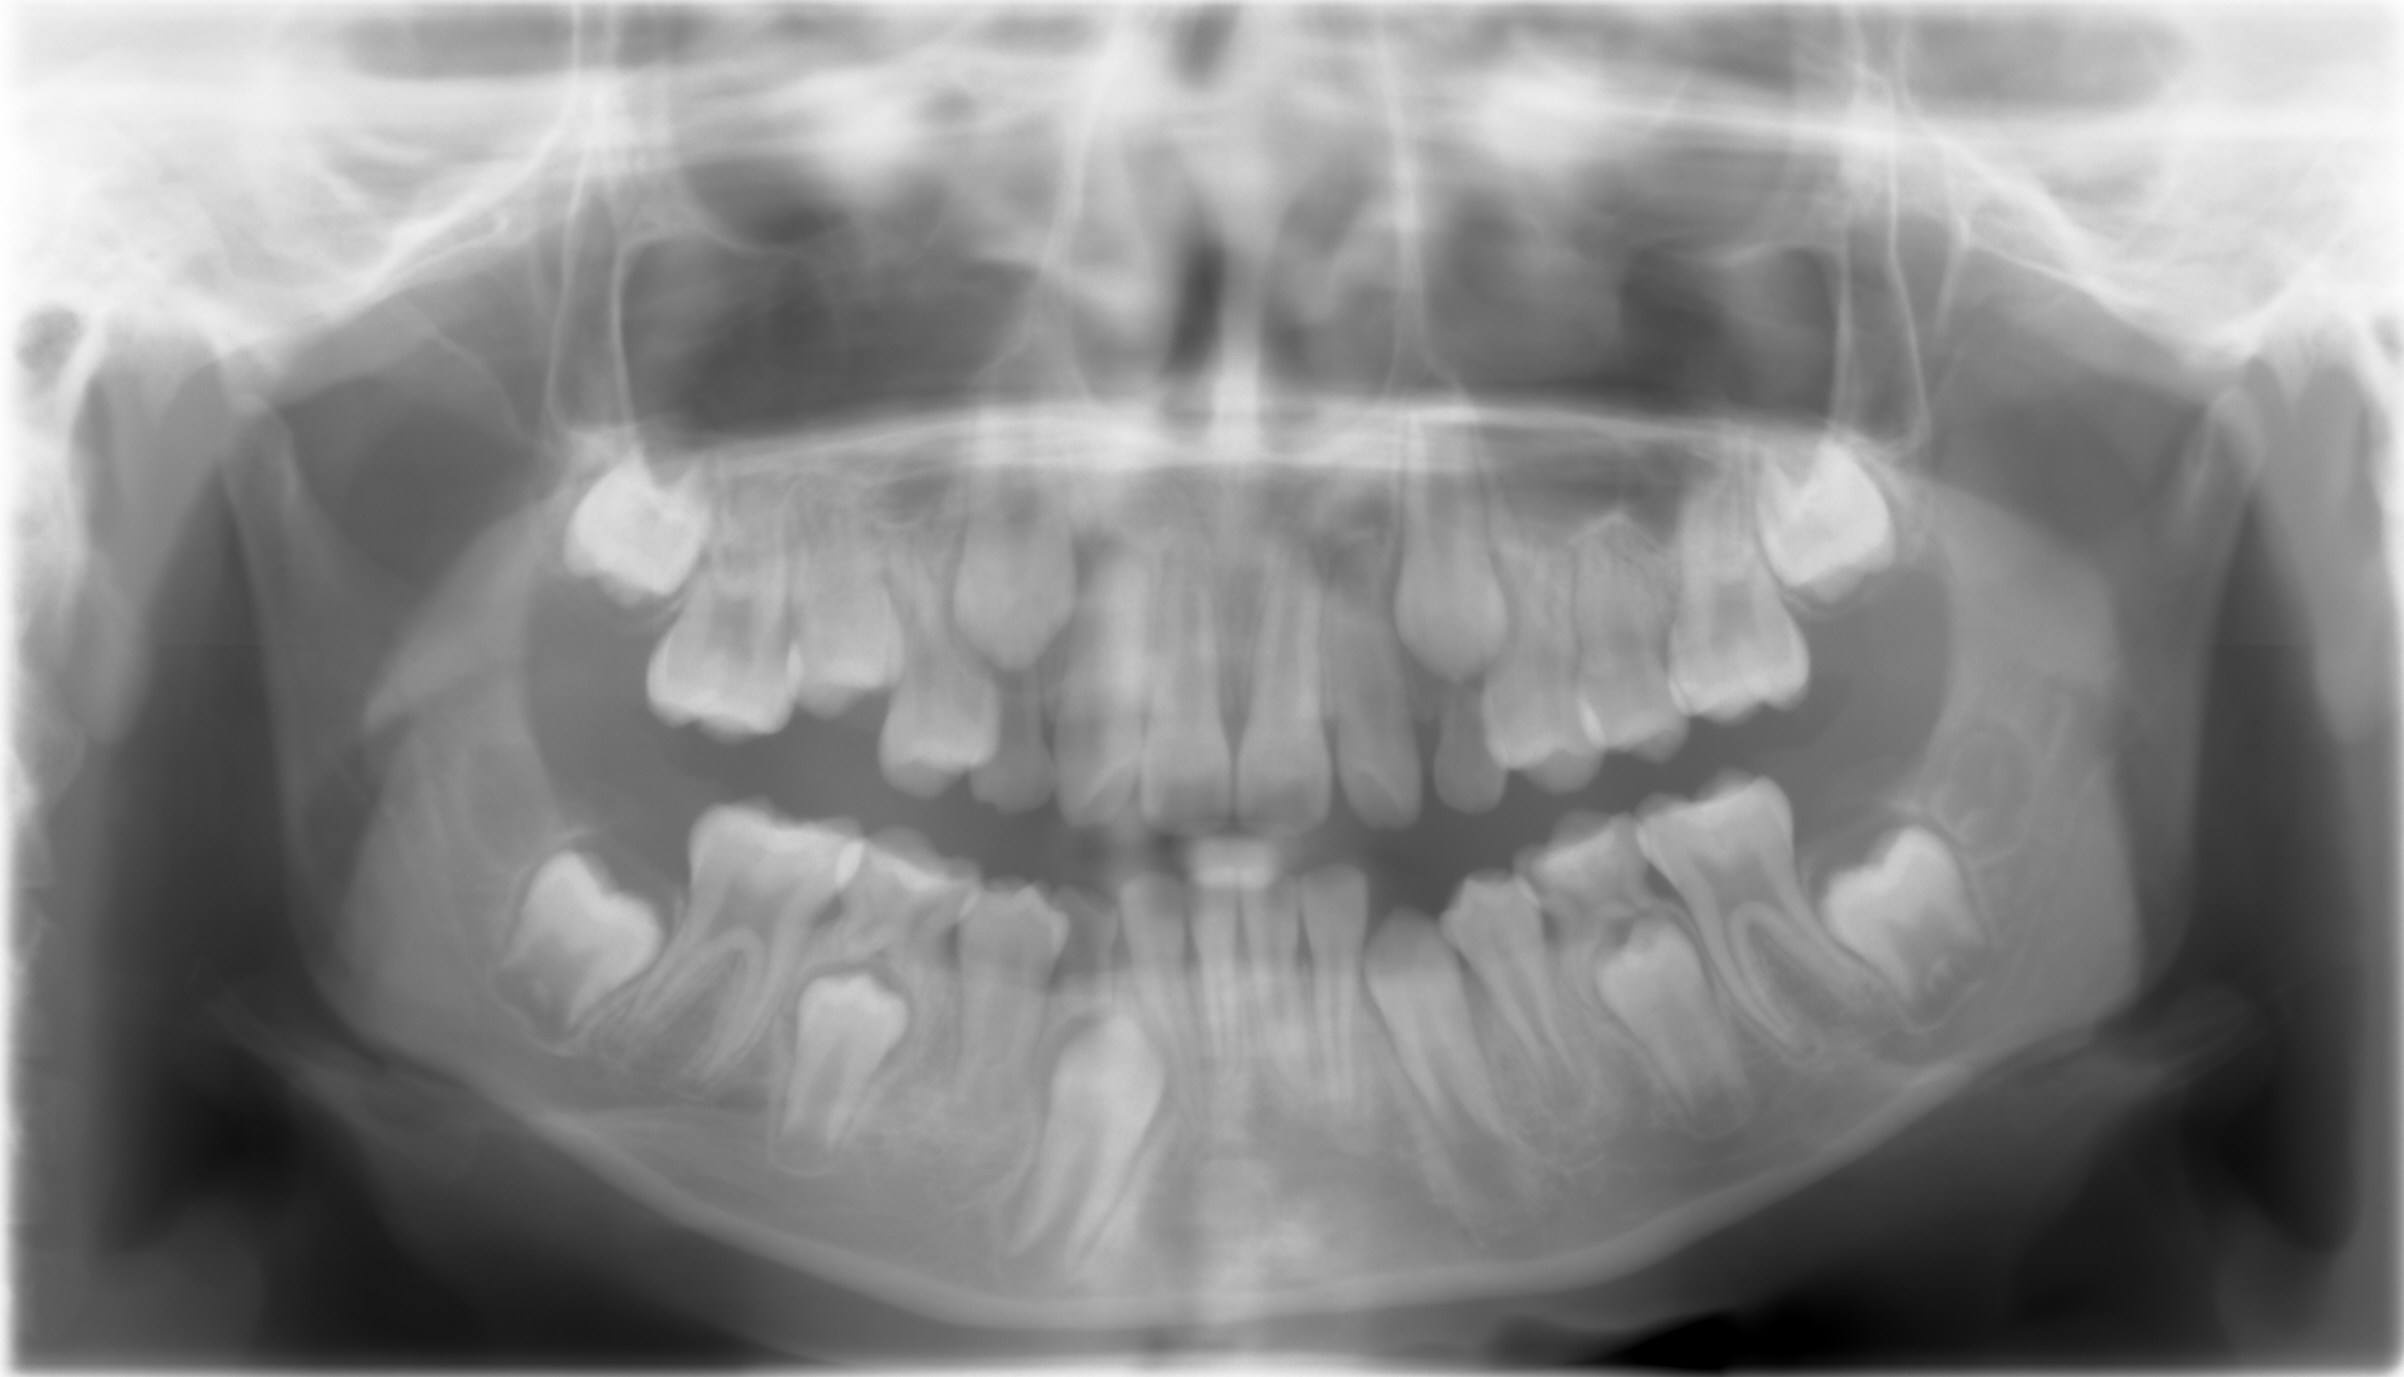

A 10-year-old boy has had Class II Division II malocclusion (Fig.1 impression taken 1 year earlier).

Panoramic X-ray (below) was taken 2 months ago.